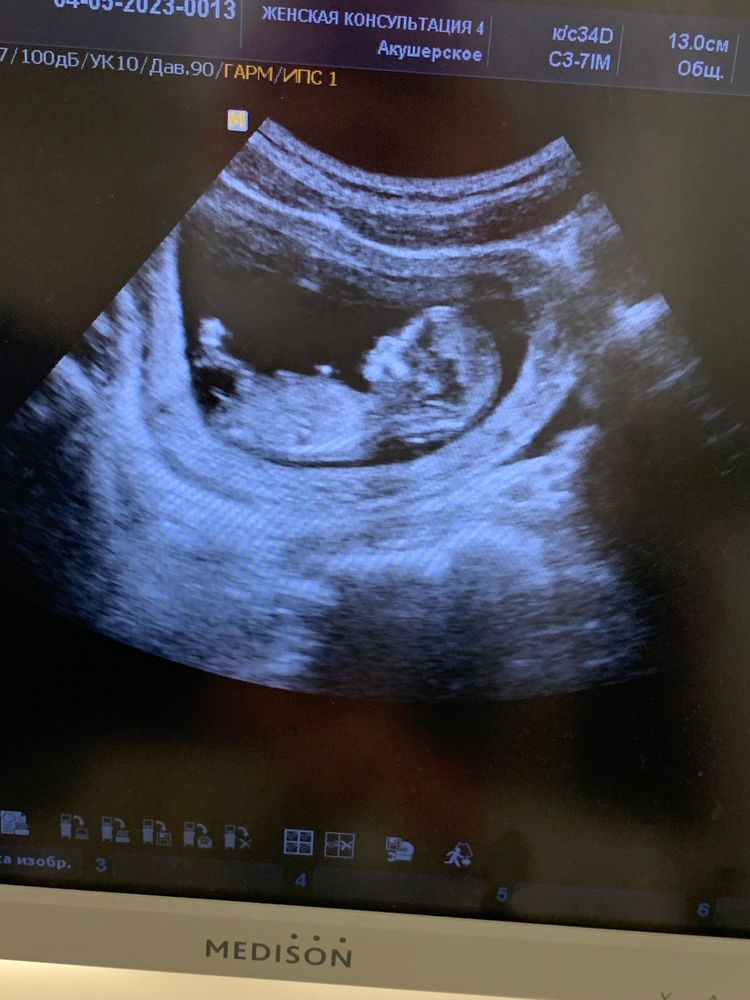

10 недель и 12 недель ☺️ сейчас он уже в экран не помещается 🥹